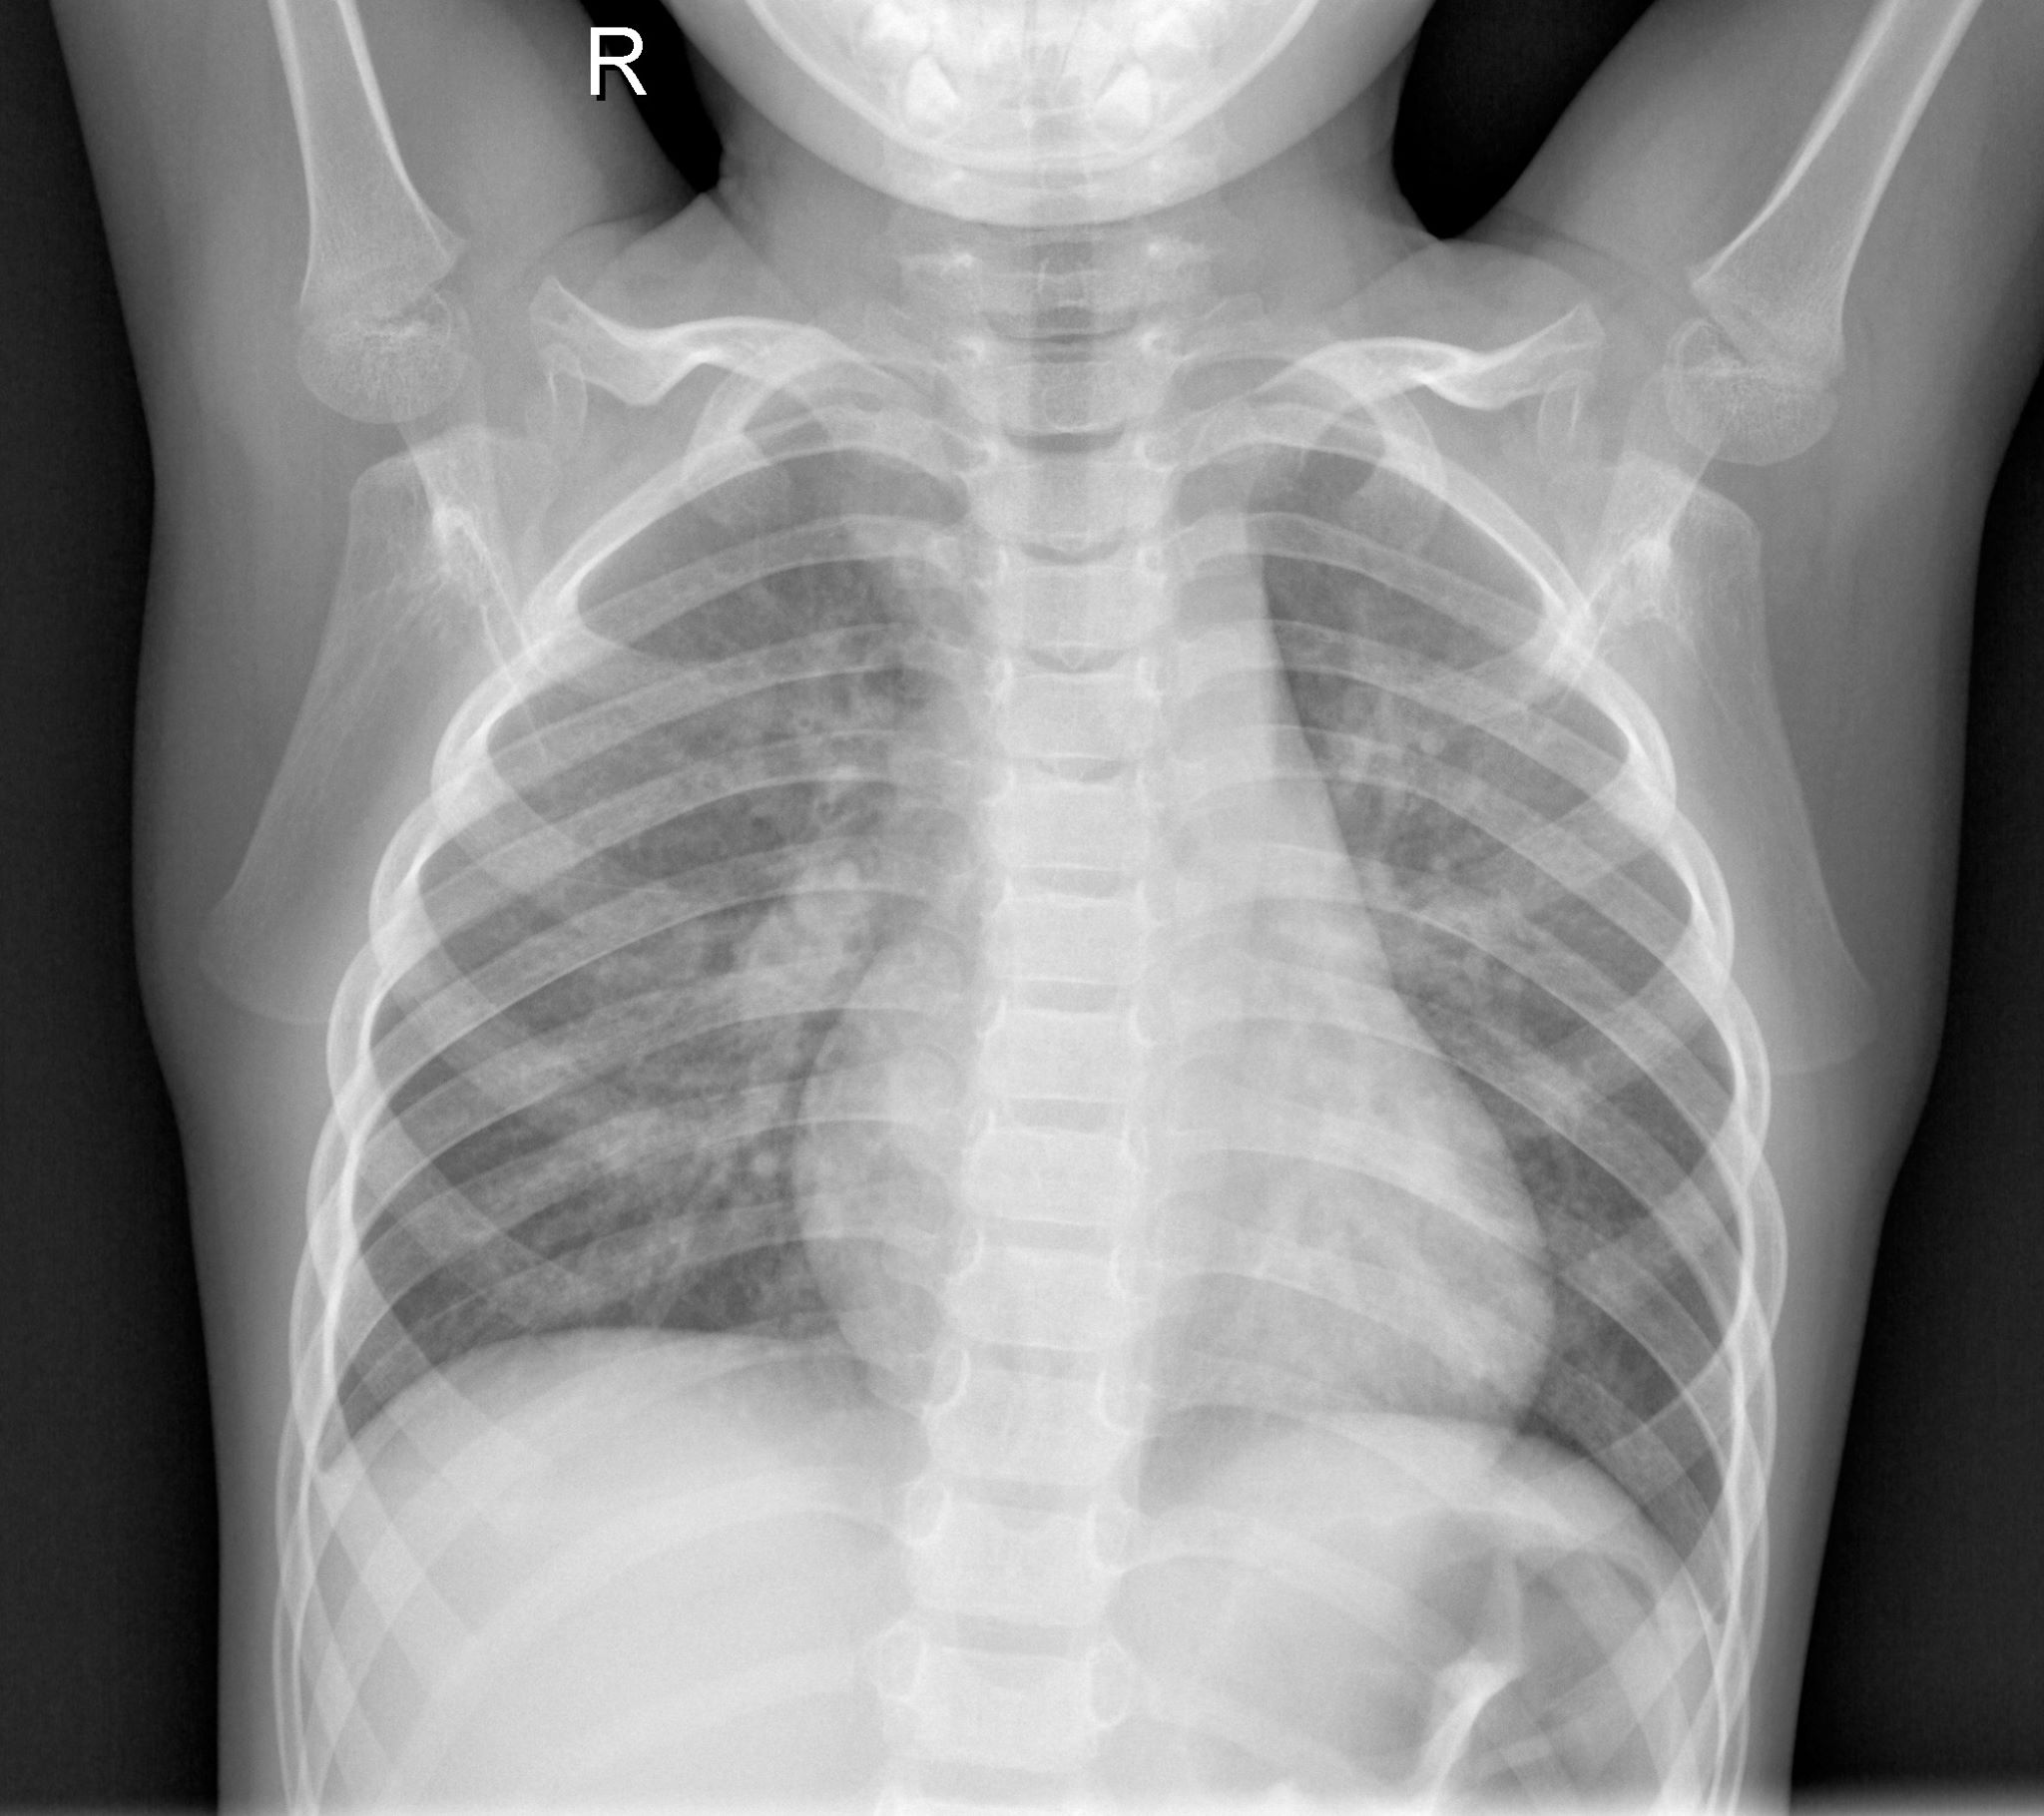

Our project takes in medical X-ray imaging from patients and classifies the X-ray images for COVID-19 using a Convolutional Neural Network (CNN) and image classification techniques.

Front-end was built as an HTML webpage that takes in X-ray images. Normalization of the images is performed (to account for orientations, inaccuracies, etc.) then the image is subjected to the CNN classification. Resultantly, the diagnosis is returned on the HTML webpage.